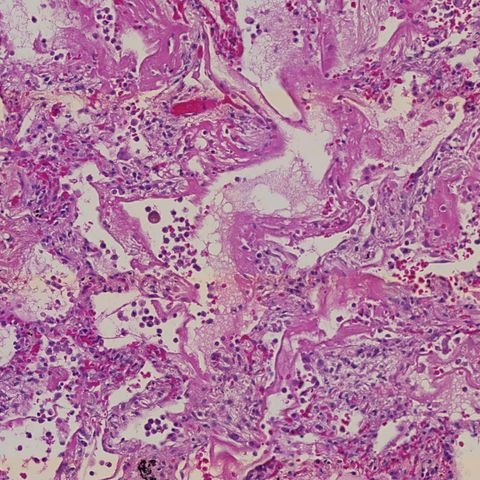

Researchers uncover cellular changes as damage to alveoli in the lungs progresses during COVID-19.

Changes in the cellular response during lung damage caused by SARS-CoV-2 – the virus behind COVID-19 – have been uncovered. Researchers reveal distinct phases where waves of immune responses give way to lung fibrosis – scarring of the lungs – in severe COVID-19.

As part of the UK Coronavirus Immunology Consortium (UK-CIC), researchers from the Wellcome Sanger Institute, Imperial College London, Newcastle University and Harvard University used a combination of cell mapping technologies to build a comprehensive understanding of the cellular response and lung tissue changes instigated during COVID-19.